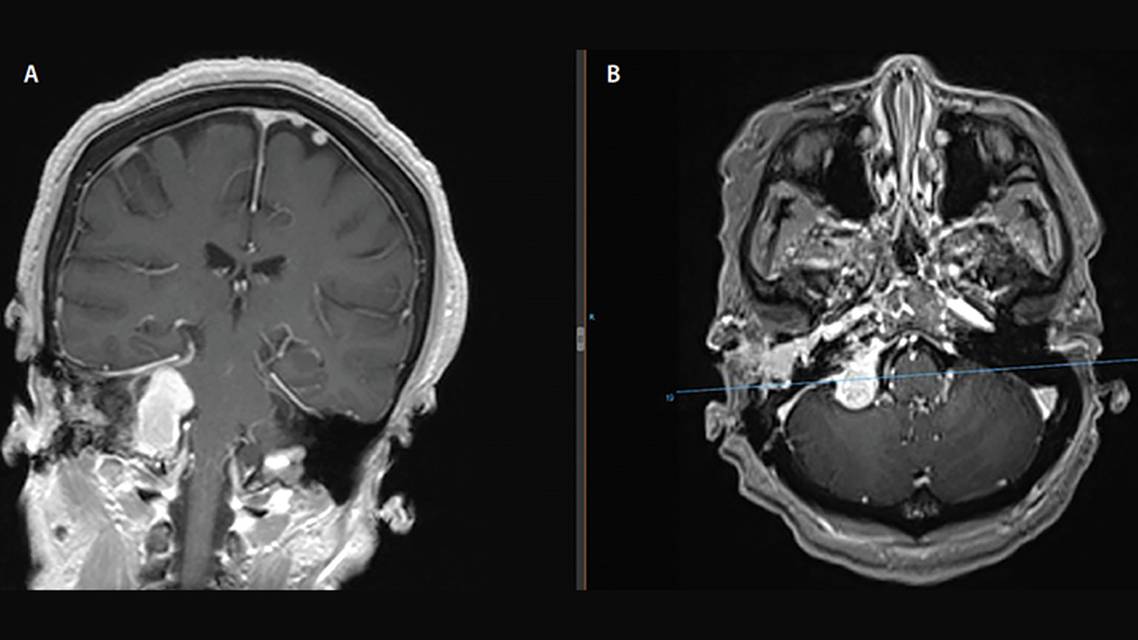

Mrs. R., age 72, was referred because of intermittent hemorrhagic otorrhea and pulsatile tinnitus in the right ear. She also reports having daily headaches and hearing loss in her right ear. On examination, she had right tongue atrophy and rightward deviation of her tongue with protrusion. Her brain MRI results showed a large predominantly extracranial right skull base enhancing lesion exiting the jugular foramen (Figure 1).